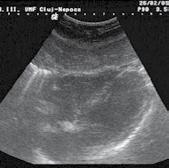

Patternuri de infiltrare a măduvei osoase în MM decelate prin IRM (figura )

Leziunile MM sunt prezente predominant în scheletul axial și anume vertebre (66%), pelvisul osos (30%) și într-o măsură mai mică la nivelul scheletului extra-axial (coaste, schelet apendicular) [20] În literatură sunt descrise cinci tipuri de infiltrare a măduvei osoase în mielomul multiplu: măduvă cu aspect normal, infiltrare focală a măduvei osoase, infiltrare difuză, infiltrare de tip “sare și piper” și infiltrare combinată focală și difuză [21, 22]; Există o multitudine de studii apărute în literatură care corelează aceste tipuri de infiltrare medulară cu modificările vizualizate la examenele morfo-patologice [23, 24]. În majoritatea cazurilor de MM (28%) se observă un aspect normal al măduvei osoase, cu hipersemnal T1 omogen al acesteia; în cazul infiltrarii, focale se observă diverse leziuni focale T1 hipointense, care pot apărea oriunde la nivelul scheletului; în cazul infiltrării difuze, se observă hiposemnal T1 difuz la nivelul intregii măduve osoase, uneori în caz de infiltrare severă, semnalul fiind chiar mai redus decât cel al discului intervertebral. În doar 3% din cazuri se observă un model de tip „sare și piper” și în 11% din cazuri se poate observa un model mixt de infiltrare nodulară și difuză [22, 25]

Tipuri de afectare medulară în mielomul multiplu: aspect normal imagistic(a), infiltrare focală(b), infiltrare difuză(c) infiltrare de tip ‘sare și piper’, infiltrare mixtă de tip focal și difuz(d). Departamentul de Radiologie al Spitalului Clinic Municipal de Urgență - Timișoara/RO